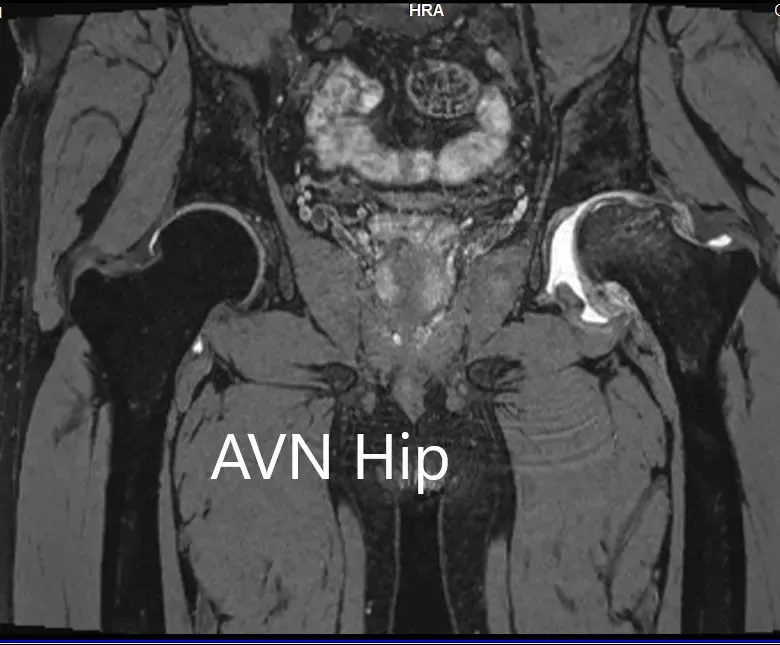

An MRI was obtained for diagnostic confirmation and staging of the disease. The left femoral head was collapsed with irregular contour and showed areas of altered signal intensity with a line of demarcation. Hypointense areas both on T1WI & T2WI seen in head suggestive of sclerosis. Surrounding marrow edema was seen

The left hip had advanced avascular necrosis with a collapse. The right hip was uninvolved presently. He was educated about the worsening collapse of the hip joint leading to his symptoms. Although the patient was young, he was advised a total hip replacement surgery in view of the collapse of the head of the femur with arthritis.